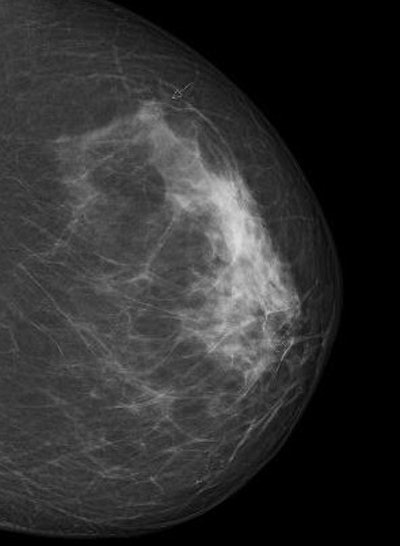

Digital screening mammogram of a 50-year-old woman taking part in the program for the first time. An invasive carcinoma was found, with precancerous microcalcifications nearby. The tumor was at an early stage. All images courtesy of Dr. Walter Heindel and the DRG.But one of the disadvantages is the possibility of a false-positive diagnosis.